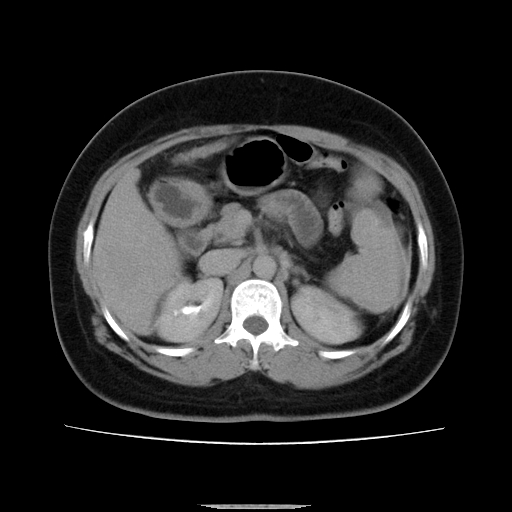

标题: CT14225:女性46岁。当地B超示肝内占位,来我院作CT检查。请 [打印本页]

标题: CT14225:女性46岁。当地B超示肝内占位,来我院作CT检查。请

右叶肝癌灶;慢性胆囊炎,不除外占位;;副脾可能性

肝内结节强化特点符合原发性肝癌表现,脾脏改变考虑为增大及先天发育所致。

符合肝癌表现,脾脏大(肝硬化?)

非常典型,肝ca,脾脏先天性发育异常,脾大